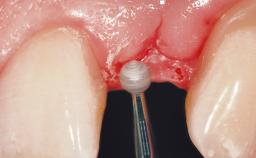

A 30-year-old female patient had lost tooth 21 and was referred to our clinic for consultation and treatment. Due to advanced apical infection, tooth 21 had been extracted two months earlier at another clinic and an acrylic-resin tooth had been bonded to the adjacent teeth. The patient desired implant treatment to avoid any damage to the adjacent natural teeth. While the patient had no history of any systemic disorder, she was a heavy smoker and exhibited medium to advanced periodontitis in the entire jaw. After the initial treatment to achieve a pocket probing depth of less than 4 mm and no bleeding on probing, a decrease in the height of the papillae mesial and distal to the extraction site and overall gingival recession were observed.

Soft Tissue Anatomy Intact Defective

Soft Tissue Contour and Volume Slightly compromised